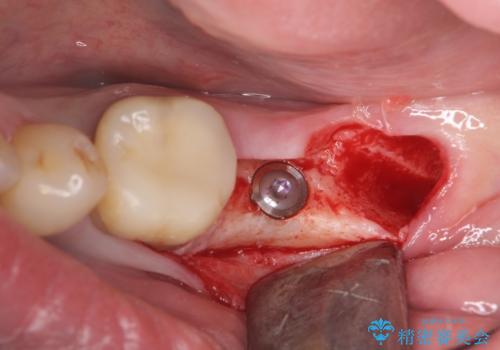

清掃性の悪いブリッジ・親知らずを除去し再根管治療・インプラントを含めた咬合再構成の計画を立てます。

- 50万円(ストローマンインプラント・骨造成・チタンカスタムアバットメント・メタルボンド×2)費用は治療当時の料金となります